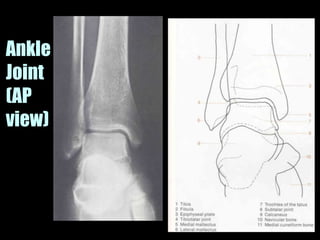

This document provides an overview of normal musculoskeletal imaging. It discusses basic x-ray concepts and densities. It then reviews normal anatomy as seen on x-rays of the skull, spine, pelvis, chest, and extremities. Key anatomical structures are labeled on example x-rays for the shoulder, hip, knee, and foot. Quizzes are included to test recognition of anatomical structures and patient age based on x-rays.